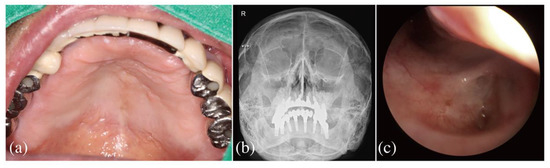

2.2. Dental Examination